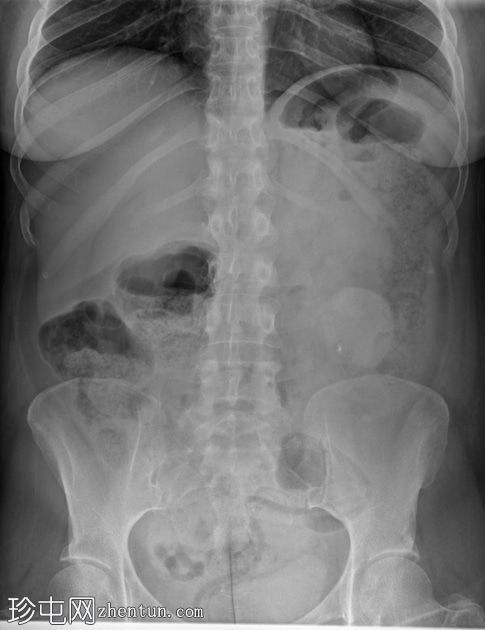

X线片

正位片

腹部X线片显示左侧腹部上方有一处边界不清的软性密度影。这代表已知的结肠造口和左侧腹部造口。

进一步发现非解剖性透亮区。这代表结肠造口袋。

可见少量粪便潴留。